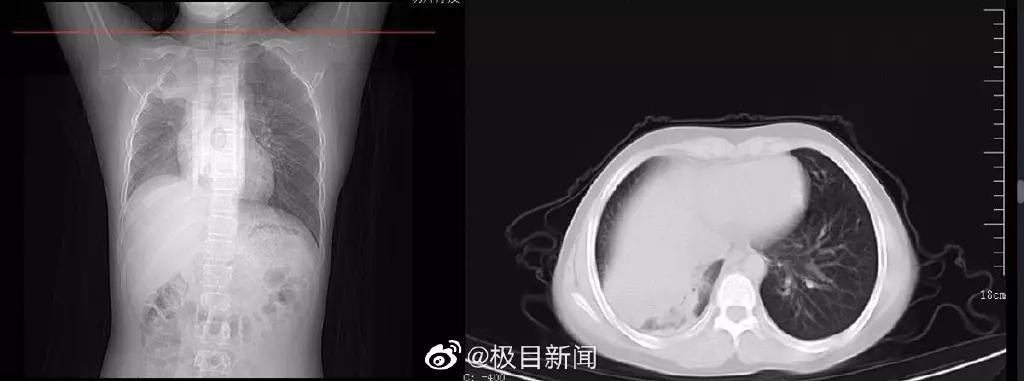

比如前几天,武汉有一位70多岁的吴婆婆,在感染之后,她没发烧、没咳嗽,所以家人们误以为老人是症状轻,没有过多在意。

但谁知,四五天,老人突然出现神志不清的症状。

急忙送进医院一看:缺氧非常严重,双肺已经白化!

这就是我们所说的——“沉默性缺氧”,又称“快乐性缺氧病”。

表面看上去好像没有什么严重的症状,实际上被死亡扼住了喉咙,非常危险。